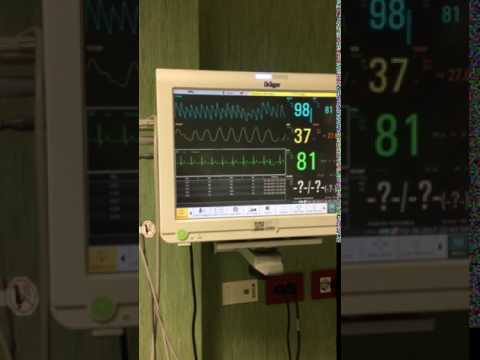

Paciente de 72 años con SCA que presenta TV polimórfica y FV que logra revertirse. Dr. Raimundo Barbosa Barros. Fortaleza, Brasil